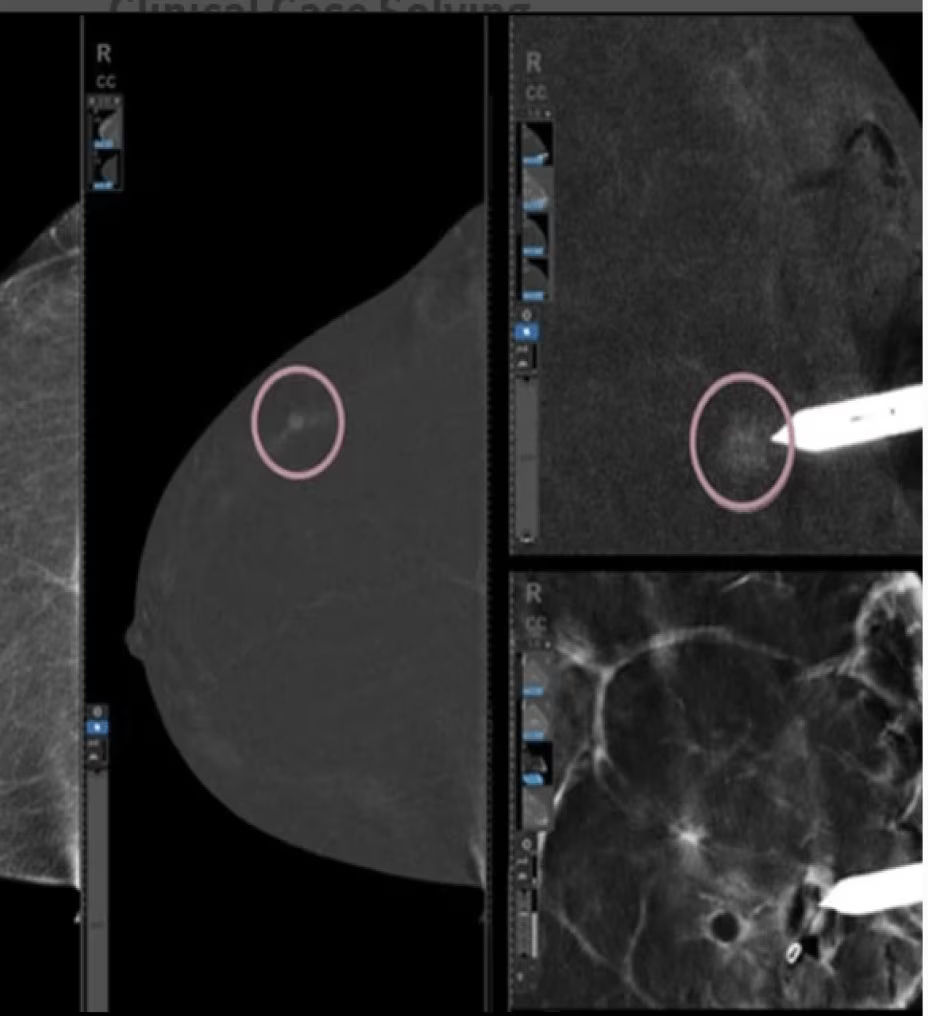

Clarity with complementary imaging

Compare like to like for increased biopsy correlation

With high sensitivity and specificity, CEM helps drive accuracy in biopsy. It allows you to clearly target suspicious areas by correlating lesion locations already identified in your patient’s diagnostic enhanced mammogram.